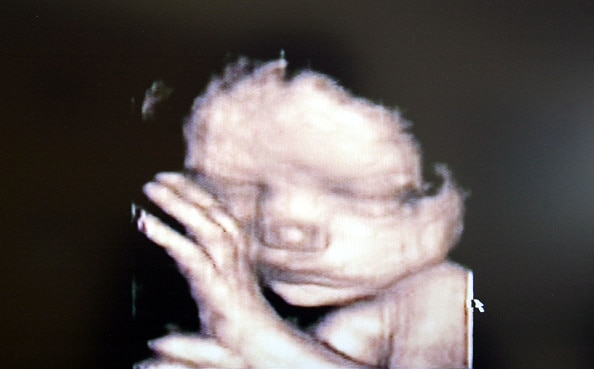

( Photo: A 3D ultrasound showing a baby inside the womb | Getty images)